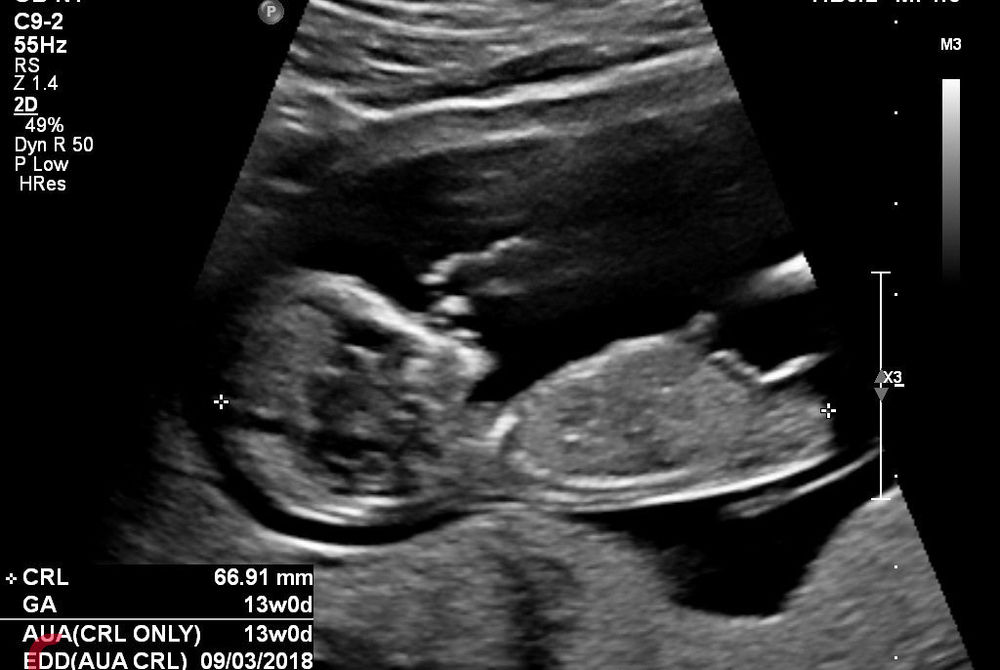

ބަނޑުގައި އޮތް ކުއްޖެއްގެ އަލްޓްރާސައުންޑް އިމޭޖެއް